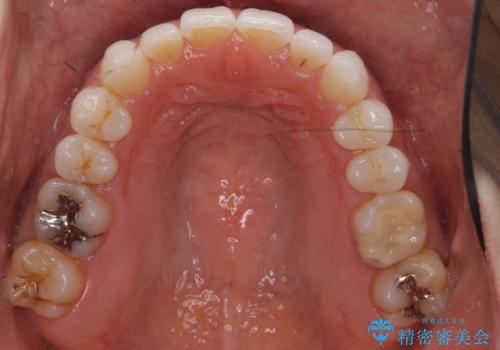

30代女性 前歯のがたつき

- 30代女性

- インビザライン

- 1年5ヶ月

- 前歯のがたつきを主訴に来院。

右下の奥の銀歯も治療しています。

- 115.5万円 矯正治療 85万円、奥歯ジルコニアクラウン11万円(ZrCr 10万円、仮歯1万円、矯正用仮歯2万円)セラミックインレー7万円費用は治療当時の料金となります

下の前歯を下げるため、IPR(歯をわずかに削る処置)を行っています。